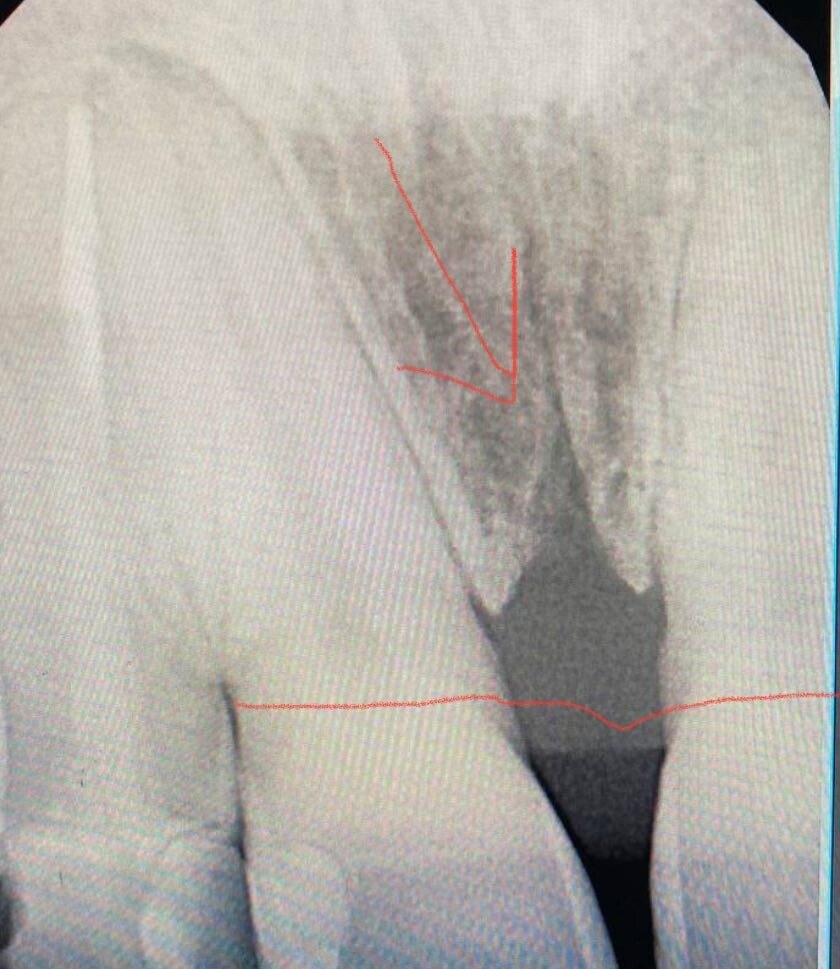

Посмотрите на этот прицельный рентгеновский снимок.

Он принадлежит взрослому пациенту, которому в детстве, к сожалению, не провели нужную профилактику.

Прямой линией показан тот уровень костной ткани, который должен быть в норме. Стрелочкой указан очаг резорбции (убыли) костной ткани, спровоцированный именно этим постоянным натяжением.